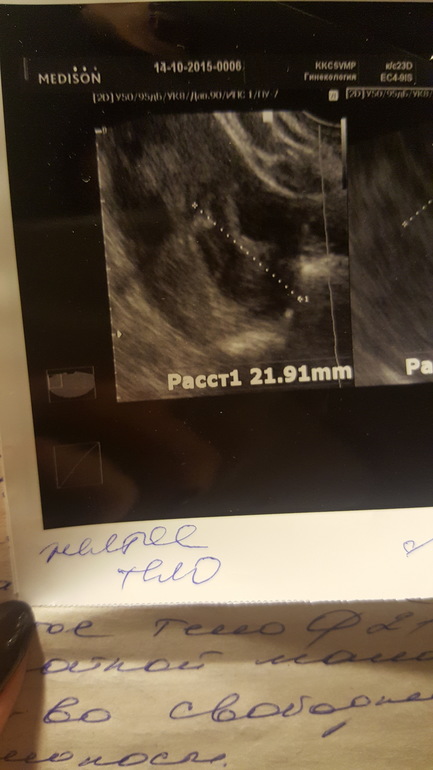

Добрый день,девочки.Дано:35ДЦ,задержка уже ну как минимум 3-5 дней...Тесты отрицательные ,на 23 ДЦ нашли в эндике включение 0,34 мм.Овуляцию чувствовала на 15-17 дц (точно не помню но не раньше ,не позже)резкая боль в ЛЯ,чуть розово-красных выд-ий.Сегодня УЗИ :Эндик 7мм(однородный)в ПЯ ЖТ 13мм??На 90%ЖТ как сказал врач.А мне вот не кажется,что это похоже на ЖТ,но я не врач,хз.В ЛЯ только фоллики..И никакого образования в Эндик нету(специально не сказала ,что там что-то находили,для чистоты эксперимента)Но когда будут М не сказали,ЖТ или нет не понятно.Да и чувствовала я 💯 процентов слева!!!Прилагаю фото,где два снимка -это сегодня ПЯ и ЛЯ,где один с точкой это включение -на 23 дц,ну и последний сегодня эндик .Как думаете,ЖТ???

фолик

и из него желтое тело